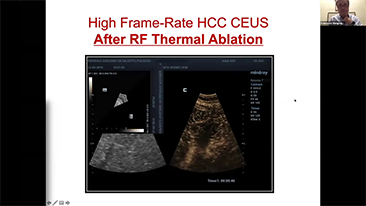

Jak wyra?nie mo?na zobaczy? w?trob??

W przypadku ogniskowych zmian w w?trobie, takich jak naczyniaki czy nowotw├│r w?troby, obrazowanie USG z kontrastem odgrywa wa?n? rol?. Technologia obrazowania USG z kontrastem UWN+ mo?e pom├│c uzyska? lepsz? penetracj?, lepsz? jako?? obrazu z ni?szym indeksem mechanicznym MI oraz d?u?szy obserwowany czas perfuzji.